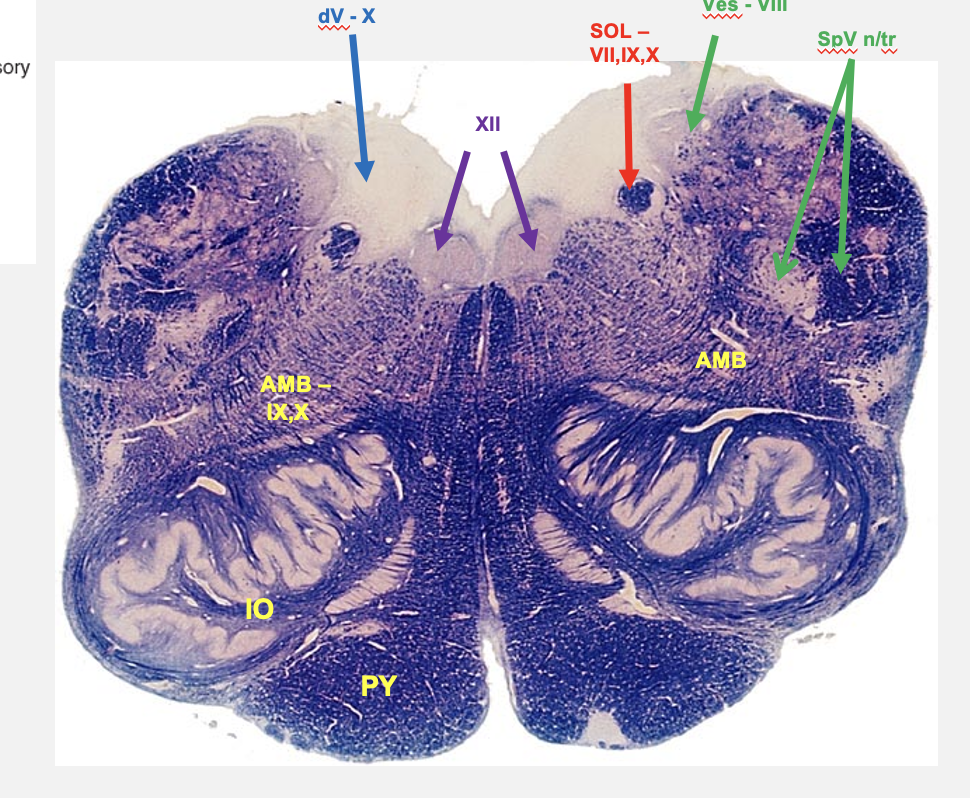

caudal medulla cross section structures

hypoglossal nucleus

dorsal visceral motor vagal nucleus

nucleus ambiguus

nucleus solitarius

vestibular nucleus

spinal nucleus of V

spinal tract of V